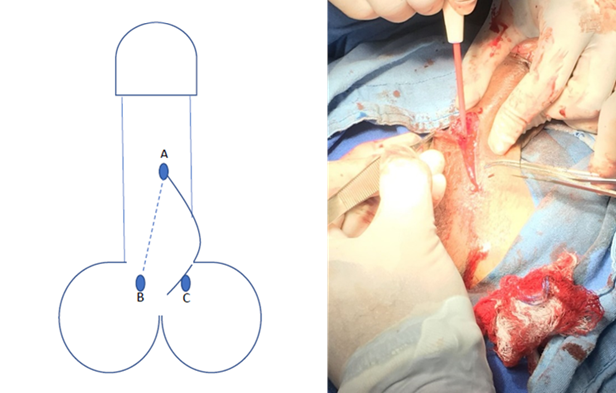

Se realiza protocolo prequirúrgico con documentación completa en el expediente clínico, ingreso del paciente para cirugía ambulatoria, con valoración anestésica, ayuno de 8 horas, baño previo al procedimiento, no se administró antibiótico profiláctico por no estar justificado, se realiza tricotomía según se necesite, se aplica asepsia antisepsia con iodopovidona. Se coloca lidocaína al 2% como anestésico local en el área quirúrgica en planos superficiales y profundos. La técnica quirúrgica aplicada en ambos casos se trata de una Plastia V-T, la cual consiste en realizar una incisión sobre la cuerda en forma de v invertida para despegar las capas de la piel de su adherencia aberrante en la cara ventral del pene (Figura 1 y 2), se afronta la nueva base del pene con sutura absorbible (Figura 3 y 4) , posteriormente se realiza incisiones laterales a la base del pene y coincidiendo a la raíz de la piel del escroto para distribuir toda la piel escrotal sobrante de manera uniforme, esto confiere la forma final de una T invertida (Figura 5 y 6).

Figura 2 Se traza una V invertida con el vértice A en la punta de la cuerda, y B y C a los lados hacia la base del pene cara ventral.

Podemos observar que posterior a la realización de la circuncisión, se realizó paso a paso la técnica propuesta como podemos observar en las Figuras 1-6 que corresponden al caso 1 que fue el más representativo de la técnica.

En la técnica propuesta se logra respetar el sentido del rafe peneoescrotal, y el la incisión horizontal permite distribuir la ganancia de la piel escrotal de una manera uniforme para que cuando el pene este en erección, la dinámica de tensión en la piel tenga piel redundante en la base y evite la formación de pliegues a la tracción, además, en las imágenes se aprecia como se logra la separación total del pene del escroto, lo cual es uno de los principios básicos de la técnica quirúrgica (Figura 2), lo cual se logra como en ninguna otra descrita.